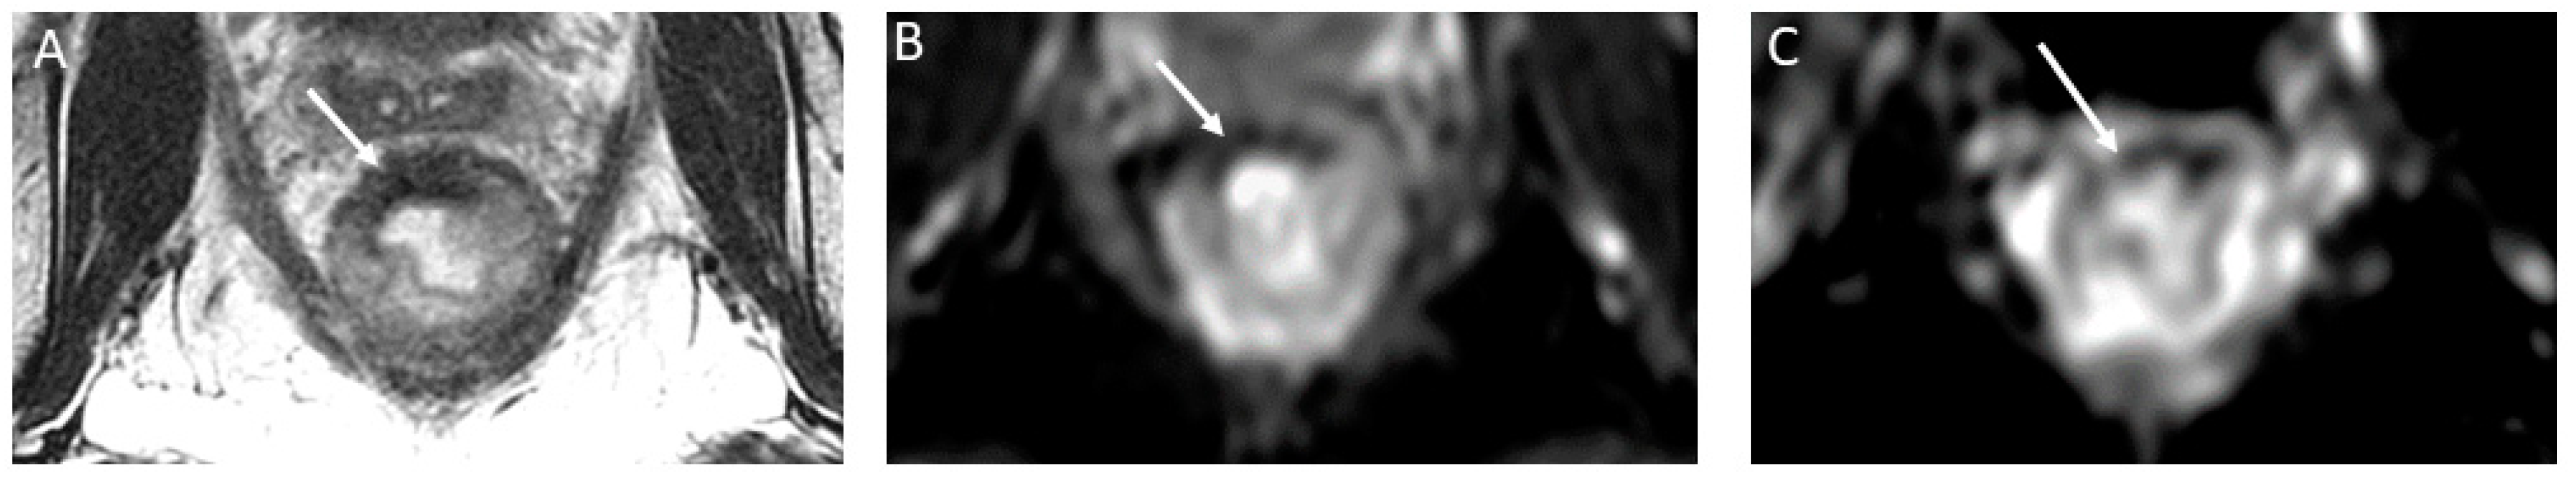

- (b)

- nCR serves as a transitional state between CR and other responses, with substantial regression evident. Of note, the term nCR emerged only recently, driven by the observation that a significant proportion of patients who display very good yet incomplete responses during the first assessment do ultimately achieve a CR when provided with a longer interval before re-assessment (26) (Figure 3). nCR retains a trace of diffusion restriction post-neoadjuvant therapy, underscoring ongoing positive changes. In cases where tumor signal or diffusion restriction persists after one or two short-term follow-up evaluations, the case should be reclassified as iCR and considered unsuitable for observation.